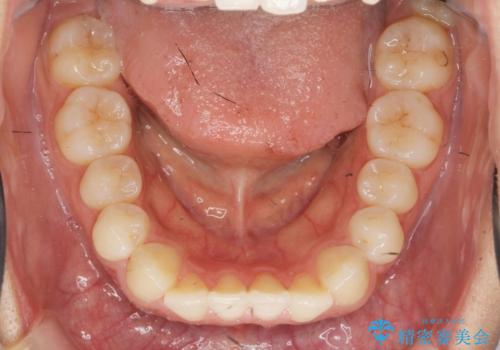

ワイヤー部分矯正を併用して治療期間を短縮 マウスピース矯正治療

- 前歯のガタつき、上下たがい違いになっている歯並び(クロスバイト)の改善を求めて来院されました。

インビザラインによる矯正治療を行いますが、クロスバイトの改善をワイヤー部分矯正で事前に行うことにより治療期間の短縮する治療計画を立案します。

上下すれ違った噛み合わせはマウスピースでは改善に時間がかかり、またねじれが残ってしまうことも多々見られます。

マウスピース矯正を行う前に、これらの症状の改善の得意なワイヤー部分矯正を行うことで治療期間を短縮し、確実にすれ違いを改善することができます。